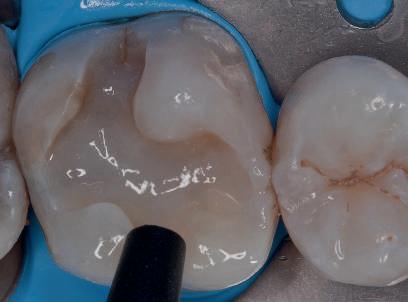

POSTERIOR COMPOSITES

Materialele compozite reprezintă un alt exemplu de proces revoluţionar al paradigmelor. Restaurările din silicat şi amalgam sunt aproape dispărute, în ciuda anumitor calităţi ce le caracterizează. Evoluţia spre compozite performante a fost facilitată de cercetările aprofundate ale proprietăţilor lor fizice, inovaţiile din acest domeniu avansând în paralel cu doleanţele estetice ale societăţii moderne.